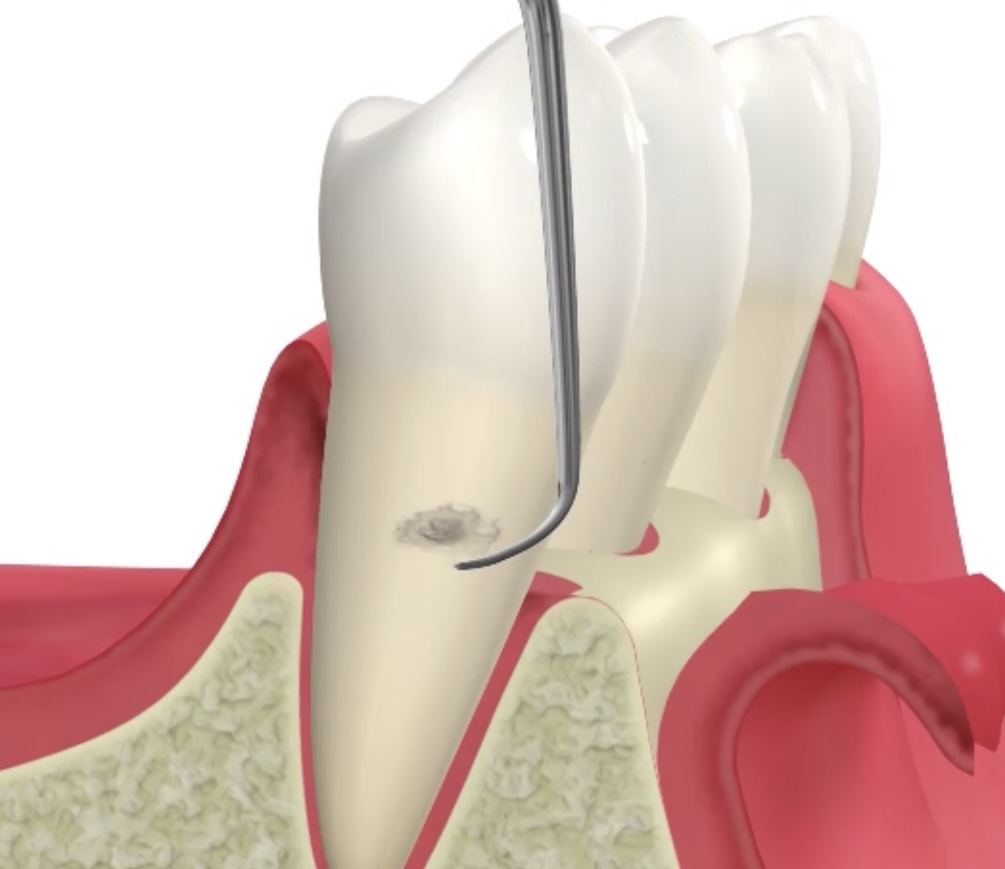

自宅で歯みがきするのと、 歯医者でクリーニングするのと、 何が違うと思いますか? 使ってる器具が専門的なもの? 特別な歯みがき粉を使ってる? いろいろ違いはありますが、 大事なポイントとして2点あげると、 ① どこに汚れがついているのか確認すること ② それをしっかり取りきること ここが違います。 お子さんの仕上げ磨きをされたことがある方はわかると思うのですが、 本人が磨いているつもりのところも、 横にしてライト当てて見たら全然磨けてないじゃん、 ということがよくあります。 大人にも同じことが言えます。 自分で磨いているつもりが習慣によってあまり磨けていないところがあるのです。 歯科医院ではその部分をより専門的に検査して確認することで、 まず磨かなければいけないところを抽出します。 50代の男性の患者さんです、クリーニング希望で来院されました。 歯みがき時の出血が心配とのことです。 上の奥歯に歯石がついているのがわかります。 ご自宅でもここまで見えたら磨けると思うのですが、難しいですよね。 まずはこの部分を患者さんに実際に見て確認してもらうことが大事です。 見ることで、普段の歯みがきの時に注意することができるようになります。 そのためにこのような写真をモニターに映して見てもらっています。 また、歯石の付着位置、歯周病の進行を確認するために、 レントゲン写真を撮って検査します。 矢印の部分に歯石が付いていることがわかります。 歯石が歯ぐきの周りに付いていると歯周病が進行して、 やがてグラグラして歯が抜けてしまいます。 そうならないためにも、 クリーニング(歯石を除去)することで、 歯周病の進行を阻止しなければなりません。 歯科医院の定期検診で行っていることは、この繰り返しなのです。 歯石の付着がわかったら、 それを取り残しのないようにしっかりクリーニングしていきます。 見えづらい部分なんかはマイクロスコープを使って細かく確認する必要があります。 歯石がしっかり取れていることを確認することもとても大切なポイントです。 超音波を使用した専用の器具や、先の細い器具を用いて歯と歯の間までキレイにします。 クリーニング後の検診時の写真です。 歯石が取れて、ご自宅でのセルフケアが上手にできると、 歯ぐきからの出血も改善してきます。 クリーニング後のレントゲン写真です。 歯石の付着がなく、歯槽骨(歯を支えている周りの骨)の吸収がおさまっていることを確認します。 いかがでしたか? ご自宅で毎日しっかり歯みがきしているから大丈夫、 と思っていても、 隠れた歯石が付いているかもしれません。 そのまま気づかないでいると、歯周病が進行してしまいます。 定期的に歯科医院を受診し、専門的な検査、施術を受けることで、 歯周病を確実に予防していきましょう。 桶川市で歯科医院をお探しの方は、ぜひ一度アズ歯科桶川院へお越しください。 治療期間 1ヶ月 治療費 保険診療 治療のリスク 定期的にチェックする必要がある